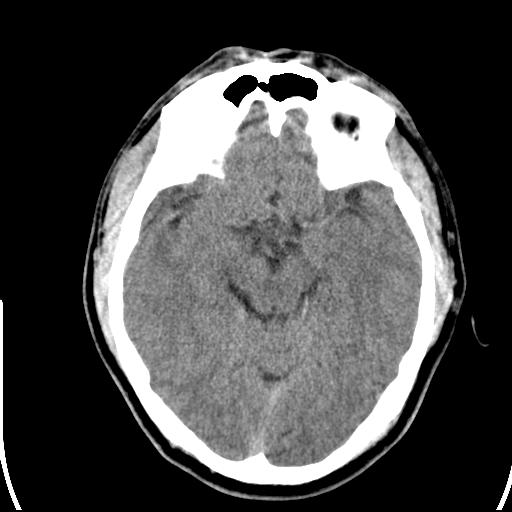

头皮下高密度结节影???临床上在老年男性比较常见。大家看看是什么?成因是? 本例患者,男性,51岁。外伤来诊。无染发史及发根植入史。

考虑异物。

皮下钙化点

没见过,可能为毛囊钙化。

考虑钙化。

这种东西有时要结合触诊和望诊。